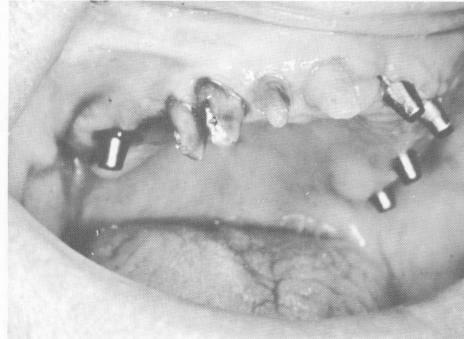

Fig. 15-35. The lower teeth were prepared and blade-vents were placed in both edentulous areas.

4 Lower teeth prepared, blade-vents implants placed in edentulous areas